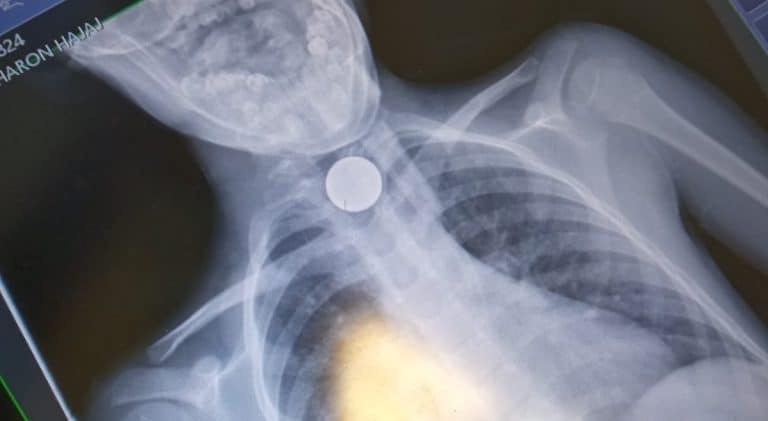

בן 7 ניצל לאחר שנחנק ממטבע כסף

צוותי הרפואה של איחוד הצלה הצילו הערב ילד בן 7 לאחר שזה נחנק ממטבעה של 10 אגורות בביתו שבבני ברק, הילד פונה לבית החולים כשמצבו יציב

- שמחה חסיד

- 14/12/2021